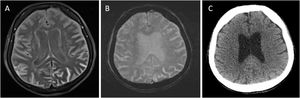

Más datosA 65-year-old female monitored in the ICU for severe hypertension (225/120mmHg) developed sulcal hyperintensities on FLAIR on day one after contrast-enhanced MRI, raising suspicion of subarachnoid hemorrhage (SAH) (Fig. 1A). However, SWI and CT showed no hemorrhage (Fig. 1B and C). The findings were attributed to gadolinium leakage, confirmed by normalization on follow-up imaging. Recognizing this prevents misdiagnosis and unnecessary interventions. This case highlights that conditions leading to blood-brain barrier disruption may allow gadolinium to leak into the subarachnoid space, which may mimic SAH on FLAIR sequences obtained after contrast-enhanced MRI. In such cases, the use of additional imaging modalities, such as CT and SWI, is crucial to avoid misdiagnosis and unnecessary interventions.